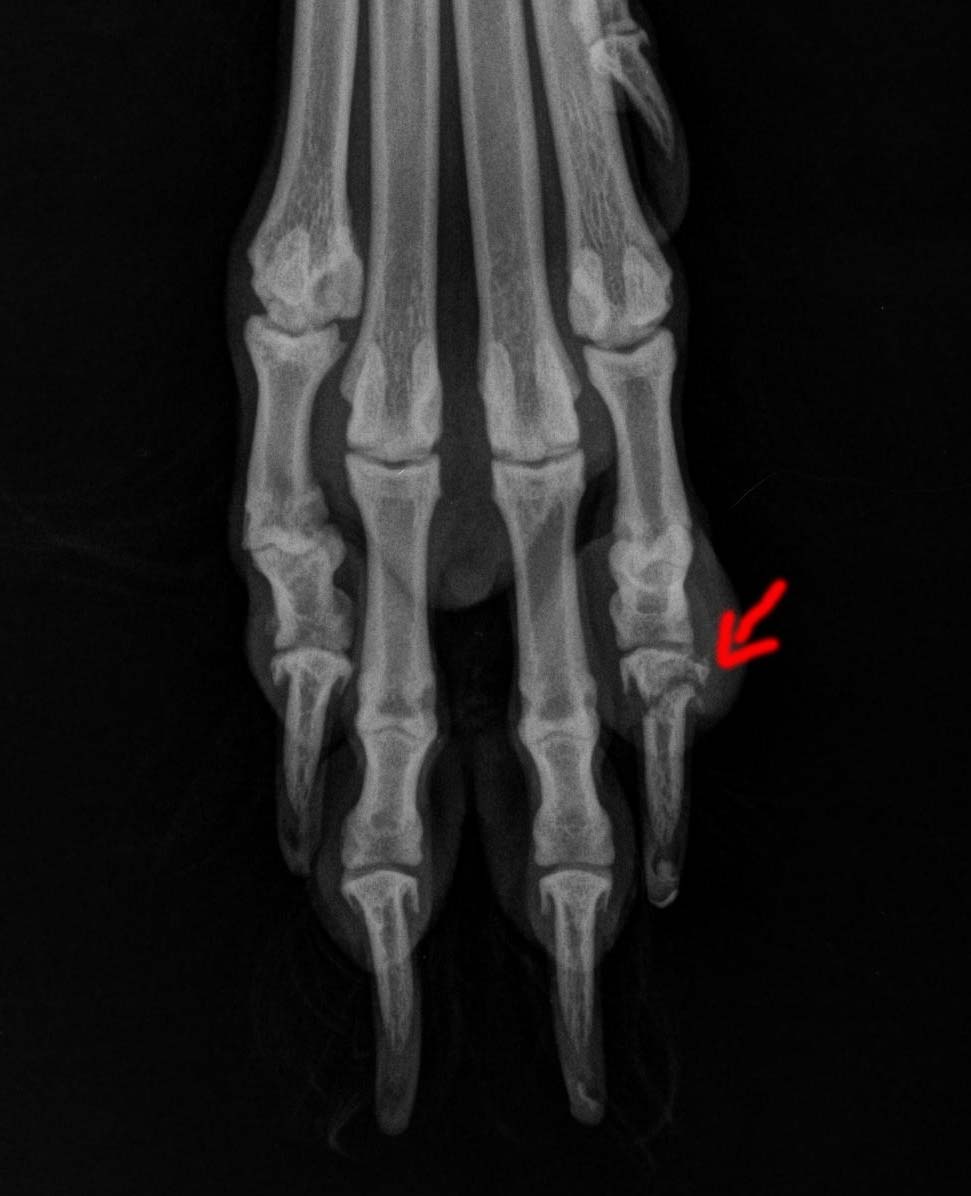

Là, la même véto (une très sympas qui ne nous a pas fait payer la consultation car pour le même problème. J’apprécie). Elle lui fait faire une radio de la patte. Verdict :

Fracture de la dernière phalange

De nouveau anti-inflammatoire + bain de patte pour garder le tout propre + repos total (le plus dur car elle est très vive quand elle ne dors pas) pendant 2 semaines et nouvelle visite pour voir si ça va mieux. Le problème résidant dans le fait que c’est une zone qu’ils ne peuvent pas plâtrer ni opérer car pas super pratique (à ce que j’ai compris). Si ça ne va toujours pas mieux il faudra envisager de lui amputer le doigt.

Mais voilà quand il s’agit de ma chienne j’ai tendance a vite paniquer, j’aimerais donc savoir si vous avez connu une situation similaire et comment cela c’était terminer. Car voilà après 4 semaines on voit bien sur la radio que la fracture est encore bien présente. Je ne suis pas la la journée en semaine et je sais que ma mère ne surveille pas ma chienne (du jore si le facteur sonne elle lâche ma chienne qui va courir après et sauter les 4 marches de la devanture de la maison… :angryfire: ya mieux comme repos total). Je sais qu’un chien peut très bien vivre avec un doigt en moins mais une opération me fait quand même un peu peur…